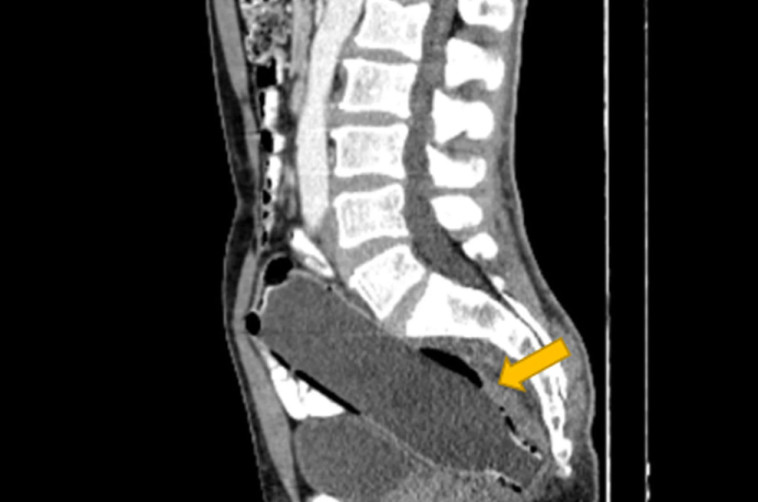

בקבוק באורך 19 ס''מ בפי הטבעת

לפי הדו"ח הרפואי, האיש נמנע מלספר על שהחדיר את החפץ בעצמו לפי הטבעת, בשל "מבוכה" ו"פחד מאשתו". עוד נאמר, כי הוא הכניס את הבקבוק פנימה כשחלקו העליון כלפי חוץ כדי שיוכל להשתמש בו כאחיזה ולשליפה אך כשהגיע הזמן לעשות זאת, החפץ נתקע ונותר לכוד במעי הגס של האיש.